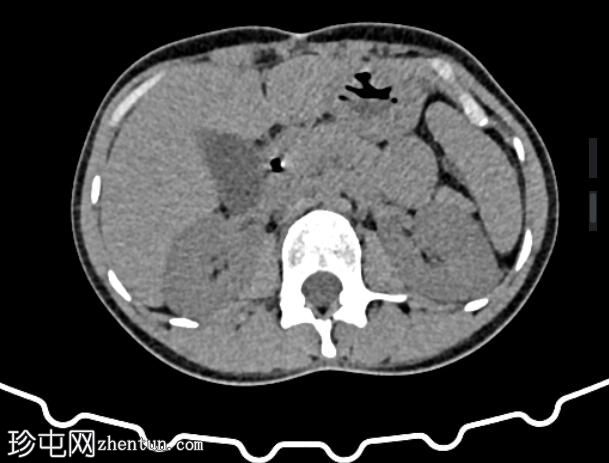

CT

轴位

肝外胆管、肝内胆管及胆囊内可见气体。后续增强(静脉)检查中加用口服造影剂,结果显示造影剂从十二指肠反流至胆总管,最终进入胆囊。